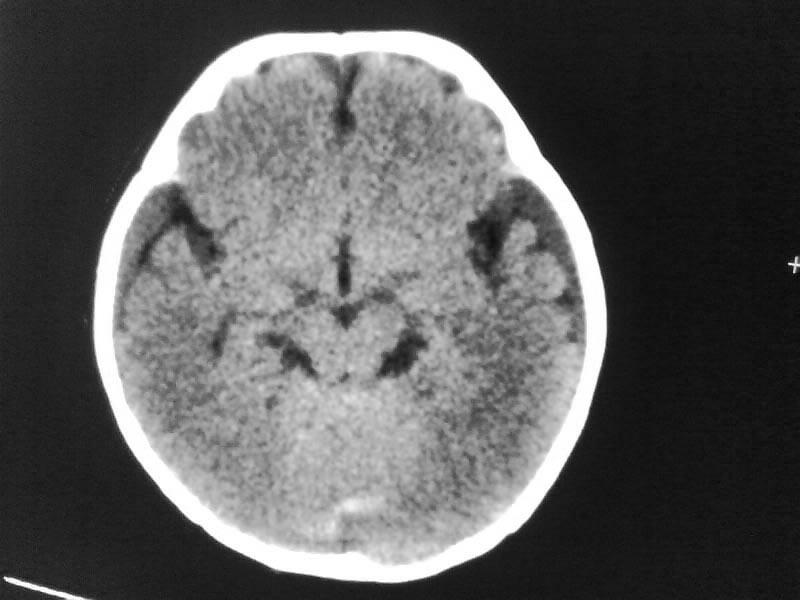

以下是引用随光逐影在2009-4-15 17:59:00的发言:[br]1)右侧额颞顶部硬膜下血肿。2)外部性脑积水。